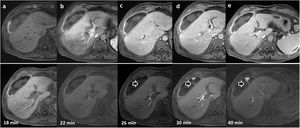

In our experience, in patients strongly suspected of having bile leak who also have perihepatic collections, it is advisable to perform an MR cholangiogram, acquiring the images later than the usual HBP, as sometimes the excretion is slowed and the leaks may go undetected in the early stages of biliary excretion (Fig. 10).

62-year-old patient with collection detected on ultrasound after cholecystectomy. Dynamic liver study with Gd-EOB-DPTA. Top row: (a) without contrast; (b) arterial phase; (c) portal phase; (d) late phase; (e) transition phase. Bottom row: sequential uptakes during the hepatobiliary phase and additional uptakes that allow the identification of extravasation of the contrast material (arrows) towards the collection in the images at minutes 26, 30 and 40.